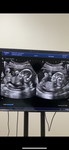

มีใครครบกำหนดวันนี้บ้างค่ะ 11 กุมภาพันธ์ แต่ยังเงียบกริบอยู่เลยค่ะ

บ้านนี้ครบกำหนดวันนี้ 40 วีคพอดี แต่น้องยังดิ้นอยู่ในท้องอย่างสบายใจอยู่เลยค่ะ หมอนัดอีกทีวันที่ 13 นี้ ไม่รู้ต้องโดนอะไรบ้าง กังวลไปหมดเลยค่ะ

กำหนดวันเดียวกับเลยค่ะ หมอนัดไปกระตุ้นปากมดลูกวันที่13ค่ะ